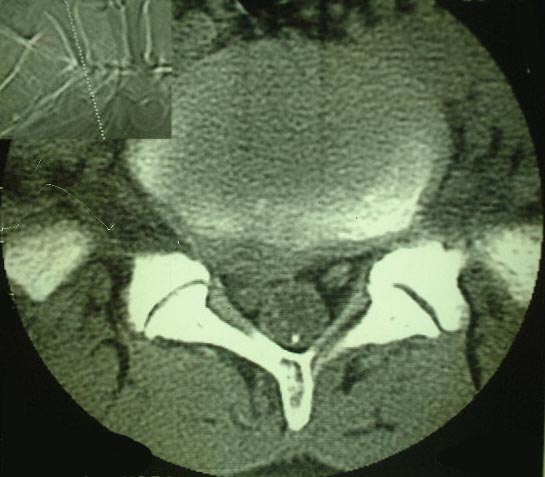

CT

CTの特徴はMRIに比べ骨の情報がよく観察できます。病変が骨由来の症例では優れた診断能力を発揮します。すなわち、CTは骨腫瘍や骨折、靭帯骨化、骨膜反応、石灰化の描出には特に有益な情報を与えてくれます。